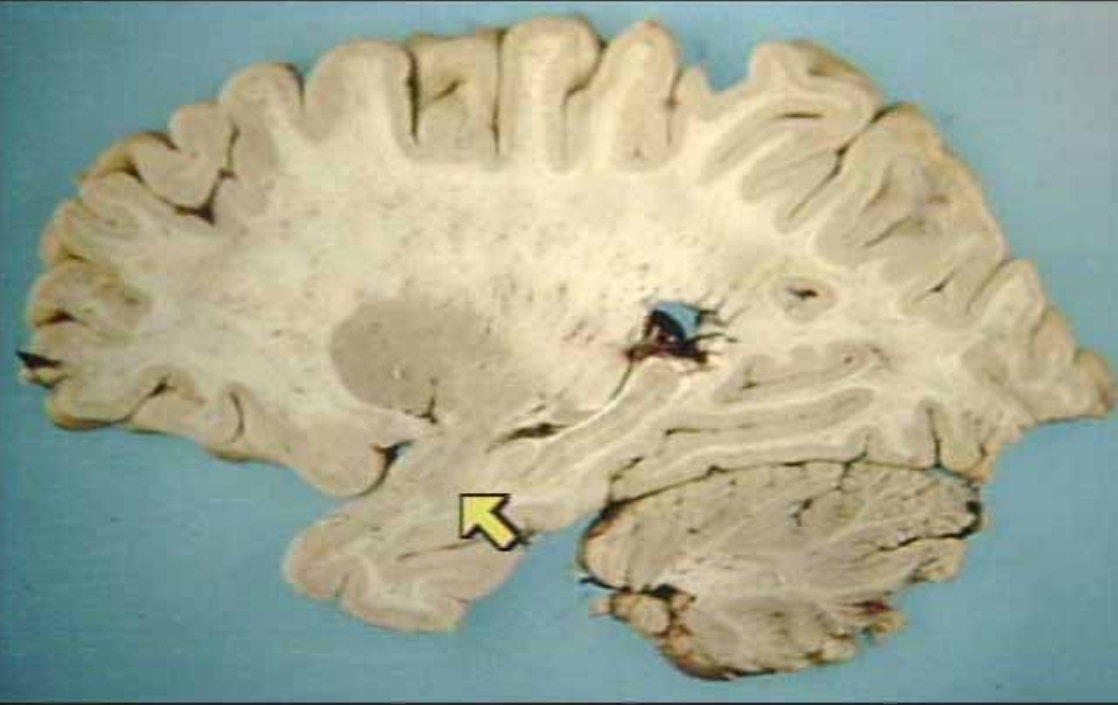

What is the arrow pointing at?

Hippocampus